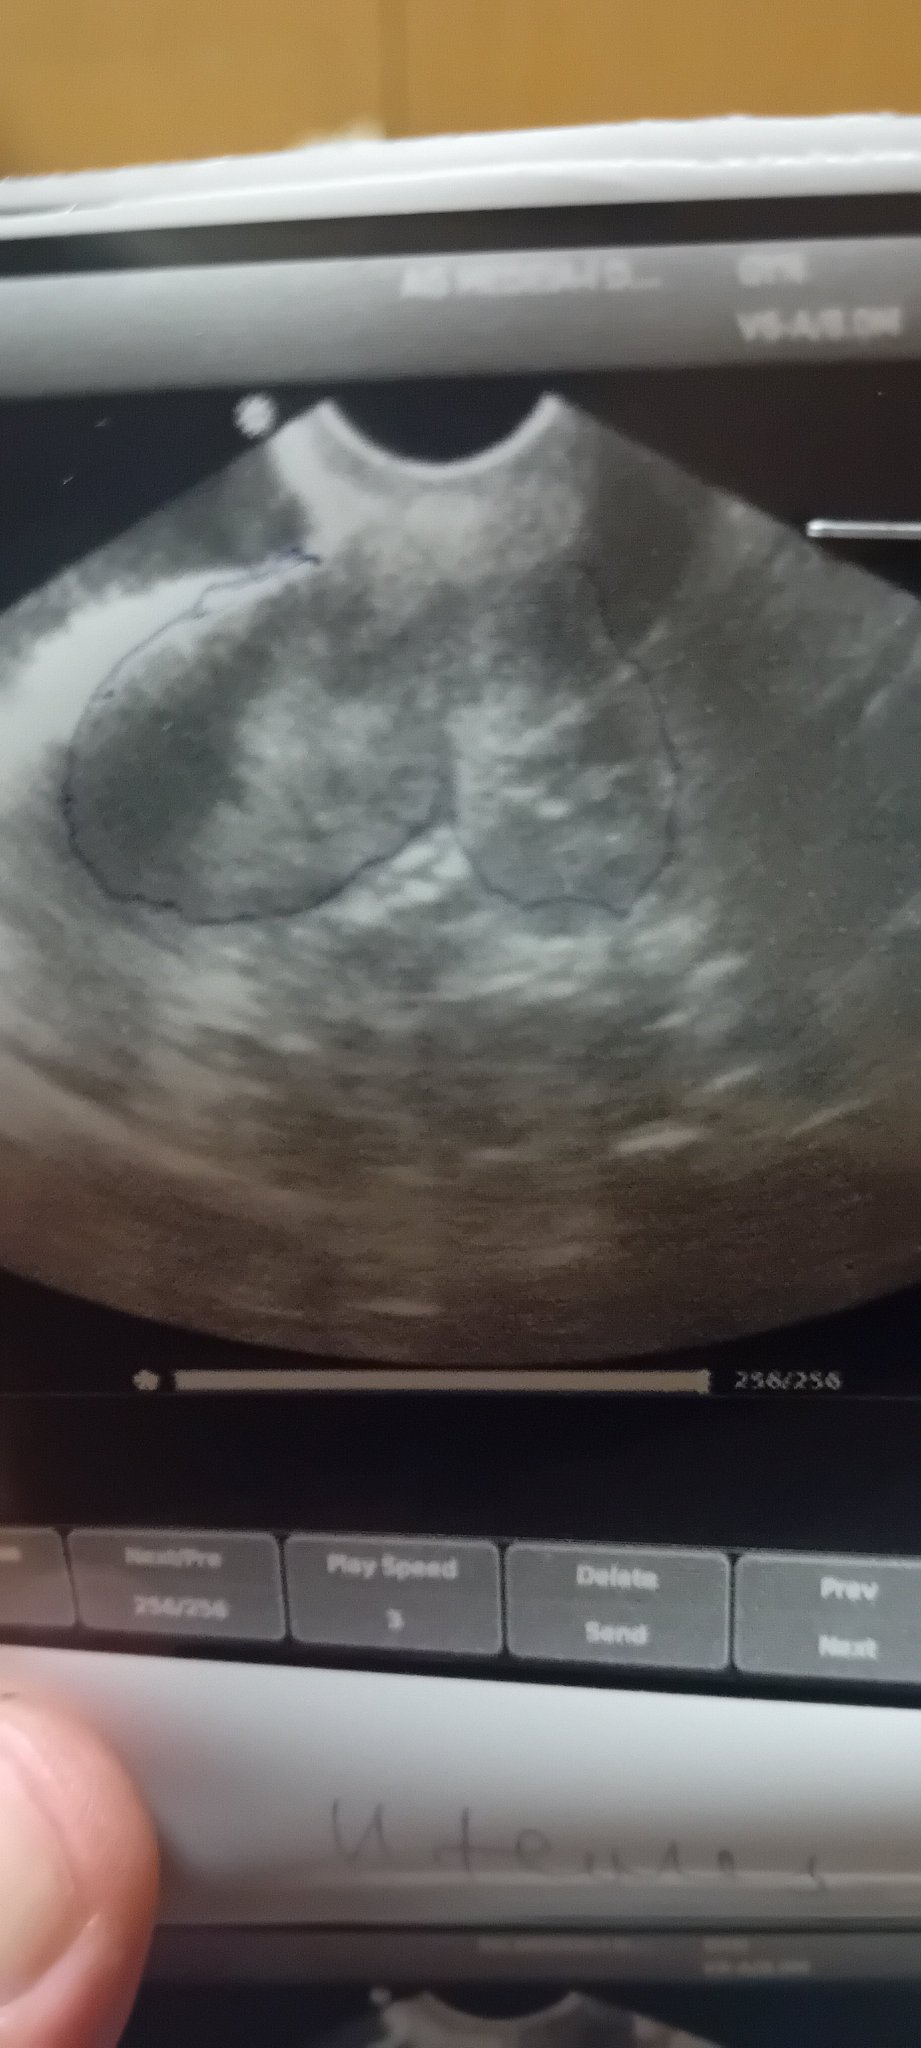

В крайна сметка родихте ли. Днес ще си направя тест. Ето ми я кистата. Но все пак съм на 44 г